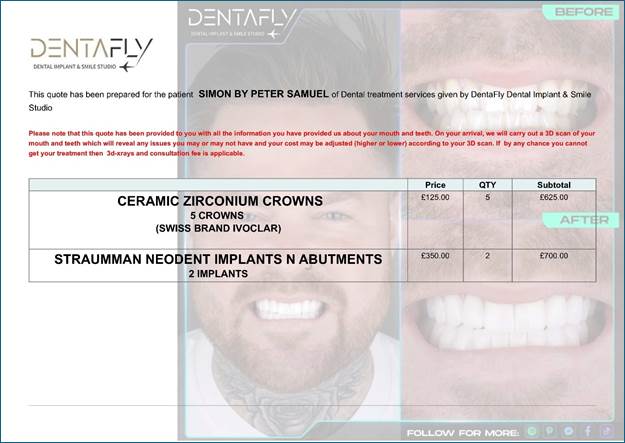

What

was finally agreed in my phone consultation with Dentafly was the following as

attached in a Copy of the invoice that they sent to us: --

To AI Edge Ok I went to turkey to Antalya

to a company called Dentafly but before I left I sent picture through what’s

app of my teeth and received a quote of 1325 pounds the invoice stated I will

receive STRAUMMAN NEODENT IMPLANTS N ABUTMENTS

2 IMPLANTs but when I got there I see their head dentist and he

advise me to get better ones named Hiossen NH Hydrophilic Implants and one

extra crown which we never realized I needed. He quoted 375 for the extras.

The price of the crows is £125 pounds as in the invoice above, so he charged

an extra £250 pounds for the implant upgrades as I was told. I have got home now and

checked the first invoiced and it has a section with pictures and texted

titled as Dental Implants Which brands we are working with and

states Hiossen NH Hydrophilic Implants 490 pounds and Straumann BLX Implants

750 pounds. so, he charged me more and

give me rubbish ones by the pricing in their invoice. The image below is from the

invoice and proves the original Implant make!